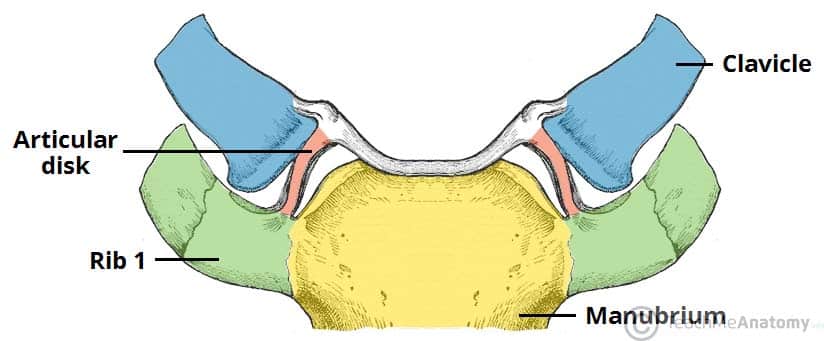

The sternoclavicular joint is formed by an articulation between three structures:

• Sternal end of the clavicle

• Manubrium of the sternum

• First costal cartilage (cartilage associated with the first rib)

The articular surfaces are covered with fibrocartilage (as opposed to hyaline cartilage, present in the majority of synovial joints). The joint is separated into two compartments by a fibrocartilaginous articular disc.

Fig 1.0 - The articulating surfaces of the sternoclavicular joint.

The articulating surfaces of the sternoclavicular joint.